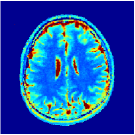

Two sets of experiments were conducted here: first, we used the 2D and 3D acquisition sequences for scanning a healthy volunteer’s brain (real-world acquisitions). Figures 6 and 7 display the parametric maps reconstructed from 2D spiral and radial readouts. We computed the T1, T2 and proton density (PD) maps using baseline reconstruction algorithms ZF, VS, LR, FLOR, AIR-MRF and our proposed LRTV. While baselines use DM either for quantitative inference or also during reconstruction (i.e. AIR-MRF), we further compare the DM-free LRTV’s performance when cascaded to DM, KM and MRFResnet for quantitative inference. For the 3D spiral acquisitions we compared LRTV and its closest competitor VS in Figure 8. Outcomes from other tested algorithm are displayed in the supplementary materials (Figure S5). Since FLOR does not use dimensionality-reduction, our system ran out of memory during 3D reconstruction; hence results are not reported in this case.

VI-E1 Discussion

The LRTV-DM and LRTV-MRFResnet perform on par, and both outperform all tested baselines for reconstructing T1, T2 and PD maps in all acquisition schemes. This can be observed both visually in Figures 6, 7, 8, S2 and S3, and quantitatively in Table IV across all tested metrics. Other baselines were unable to successfully remove the under-sampling artefacts in TSMIs, and these errors propagated to the parameter inference phase and resulted in inaccurate maps. Temporal-only priors incorporated within LR are shown insufficient to regularise the inverse problem and LR sometimes (e.g. 2D spiral acquisitions) can admit solutions with even stronger artefacts than the model-free ZF baseline. This issue was previously studied for other non-Cartesian MRF readouts that similar to our spiral/radial trajectories, miss to sample the corners of the k-space in all timeframes (see section 2.2.2 and figure 2 in [19]). In the absence of reference for the k-space corners information, the LR iterations despite minimising the objective can converge to solutions with high-frequency artefacts, as visible in the computed maps. This highlights the need for adding an appropriate spatial-domain regularisation. FLOR reduces the LR’s artefacts but this improvement is limited because the suggested nuclear norm penalty does not incorporate an explicit spatial regularisation. Further for reducing artefacts, FLOR can introduce an undesirable bias in the computed T1/T2 maps e.g. see error maps in Figures S2 and S3. The non model-based VS baseline incorporates spatial regularisation and results in spatially smoother maps than ZF and LR, but it is unable to output artefact-free images. Further and consistent with our in-vitro experiment, we observe that VS overestimates the T2 values (e.g. in White and Grey matter regions) in tested 2D acquisitions i.e. the spatial regularisation trades off agains the quantification accuracy. The model-based AIR-MRF adds spatial regularisation through 2D/3D low-pass Gaussian filters however this trades off the sharpness of the computed maps and can increase the errors at the tissue boundaries (we searched Gaussian spreads that keep the blurs and high-frequency artefacts minimal). For our acquisition readouts, Gaussian filters performed better than disk filters of [19] for avoiding strong Gibbs artefacts. On the other hand, the spatiotemporally regularised LRTV greatly improves the TSMI reconstructions i.e. 4 dB enhancement compared to the closest competitor baseline (Table IV). This enables computing accurate and aliased-free multi-parametric inference using DM or the DM-free learning-based alternative MRFResnet as visible in Figures 6, 7, 8, S2 and S3. MRResnet and DM score competitive quantitative inference results i.e. T1 and T2 MAPE less than 5% and 9%, respectively (Table IV). KM also outputs comparably accurate T1 maps, however this shallow learning model despite having a model size larger than MRFResnet, is unable to learn accurate T2/PD quantification and it results in poor estimated maps, consistent with our observations in section VI-C.